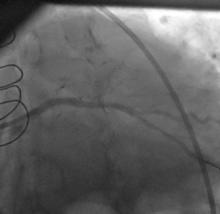

A CLs guiding catheter was used to engage the left coronary artery, and a Choicd floppy guidewire passed through the lesion. The lesion was predilated with a 1.5x15mm and 2x10mm Maveric balloon (figure 4). Then a 3.5x18mm Xience v stent was deployed at 16atm (figure 5, figure 6, figure 7). Post-dilation was done with a 4x10mm Firestar NC balloon (figure 8). The final result showed TIMI-III flow with no residual stenosis (figure 9).